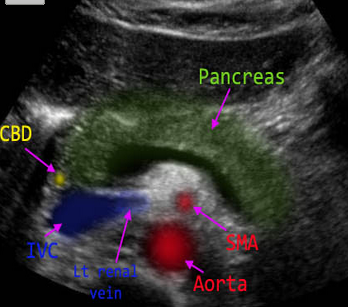

La insulina, que es una hormona producida por el páncreas, regula la cantidad de azúcar; la escasez en la producción de esta puede ser otra causa para padecer diabetes.